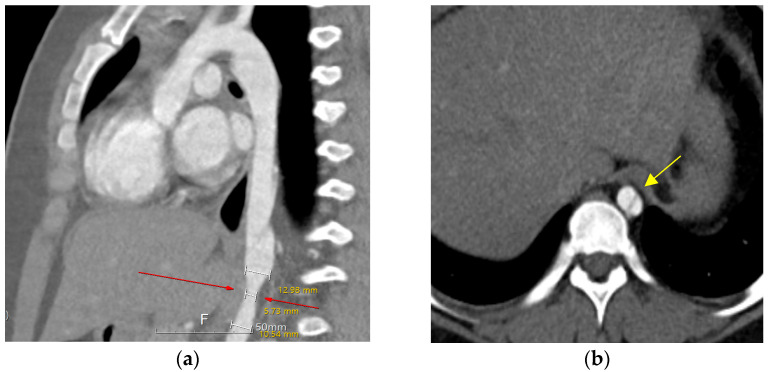

没有记录的病例导管引起的主动脉夹层的儿童患者。我们报告一个独特的情况下,儿童患者唐氏综合症谁开发了一个长期夹层主动脉瘤。患者在难以取出栓塞的动脉导管未闭装置10年后成功植入支架。唐氏综合症表现出复杂的临床情况,由于缺乏合作和不确定何时发生解剖,使得诊断具有挑战性,因为没有报告疼痛等症状。虽然在儿童中很少见,但重要的是要认识到经皮动脉导管未闭闭合后取出装置等手术是儿童主动脉夹层的潜在危险因素。

There are no recorded cases of catheter-induced aortic dissection in pediatric patients. We report a unique case of a pediatric patient with Down syndrome who developed a long-standing dissecting aortic aneurysm. The patient underwent successful stent insertion 10 years after experiencing difficulty retrieving an embolized patent ductus arteriosus device. The Down syndrome presented a complex clinical scenario, making diagnosis challenging due to a lack of cooperation and uncertainty about when the dissection occurred, as symptoms like pain were not reported. Though rare in children, it is vital to recognize procedures such as percutaneous closure of patent ductus arteriosus followed by device retrieval as potential risk factors for aortic dissections in the pediatric population.